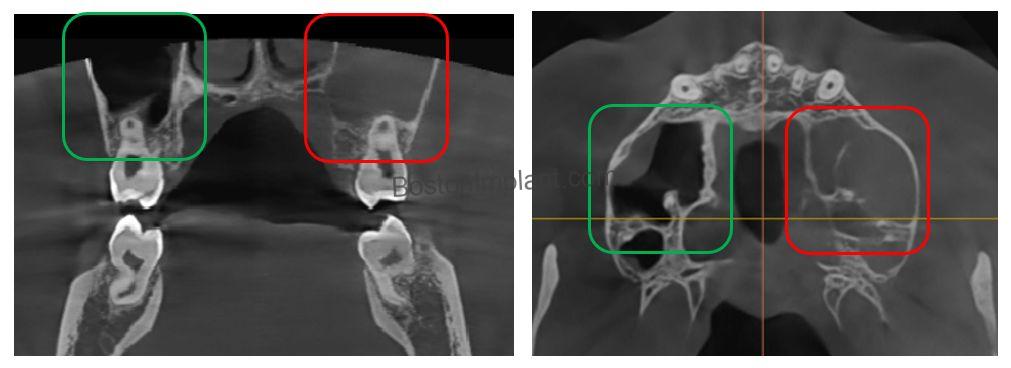

4. Sinus Issues: Last month, a 15-year-old boy was referred to me regarding pain on his upper left side. He complained of pain in his upper left first molar, but his dentist couldn’t find any issues with the tooth, which sometimes leads to unnecessary root canal treatment. I gathered more information from him. The boy complained of not only tooth pain but also pain when moving his head or running. Sometimes, sinus inflammation can cause tooth pain, and I confirmed this with CBCT.

The red square area in the image appears fuzzy compared to the green square, indicating a sinus issue. I confirmed his maxillary sinusitis by checking for seasonal allergies, and his symptoms disappeared after taking allergy medication.